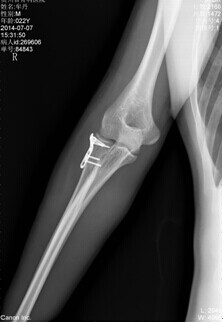

2014年7月7日,贵州省骨科医院成功地为一位桡骨小头粉碎性骨折的患者实施了手术,完美修复了碎裂移位的桡骨小头。这是该院第二次成功将3D打印技术与传统的骨科手术结合取得的成果,标志着贵州省骨科医院在数字骨科技术治疗方面又迈上了一个新的台阶。

6月30日,22岁的患者小牟由家属陪同来贵州省骨科医院就诊,据家属讲述,患者小牟曾在其他医院进行人工桡骨小头置换术。贵州省运动医学委员会主任委员、贵州省骨科医院院长邱冰教授仔细分析病情后,认为患者年轻,不适合做置换术,完全可以修复重建,提出了用3D打印技术辅助手术治疗,修复桡骨小头的治疗方案。7月1日,小牟的CT数据传到了与省骨科医院合作的数字骨科打印中心,按照原比例打印出了受损的桡骨小头模型。邱教授的治疗组进行了术前的设计,制定出可行的治疗方案。手术按照计划进行,完美的复位固定得到同行的一致认可。术后的康复也令人满意。出院前,小牟的父亲对骨科医院的专家们表达了心中的谢意。

图为通过3D技术打印出来的受损桡骨小头模型

患者影像资料